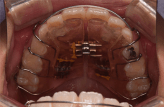

小学生のマウスピース型矯正装置とその他の装置(拡大床)の比較

拡大床の場合

治療のゴールは、顎の大きさを広げるのみです。

• 治療期間は、6~24か月。(※個人差あり)

• 取り外しは、できません。

• 基本的には、2年間同じ装置を使用します。

• 見た目は、針金が少し目立ちます。

• シミュレーションソフトは使用しません。

マウスピース型矯正装置の場合

治療のゴールは、顎の大きさを広げるだけではなく、それと同時に気になっている歯のねじれやガタガタ、隙間などに対しても細かく歯の位置を修正することです。

• 治療期間は、18か月。

• 取り外しができます。食事や歯磨きも普段通りに行えます。矯正装置による虫歯のリスクは固定式の装置に比べ格段に少ないと考えられます。

• 定期的(平均2週間に1度)に新しいマウスピースに交換していくので衛生的です。

• 透明なマウスピースを装着するので、装置をつけていても目立ちません。

• シミュレーションソフトによる治療計画の立案と治療中の経過検証が可能です。